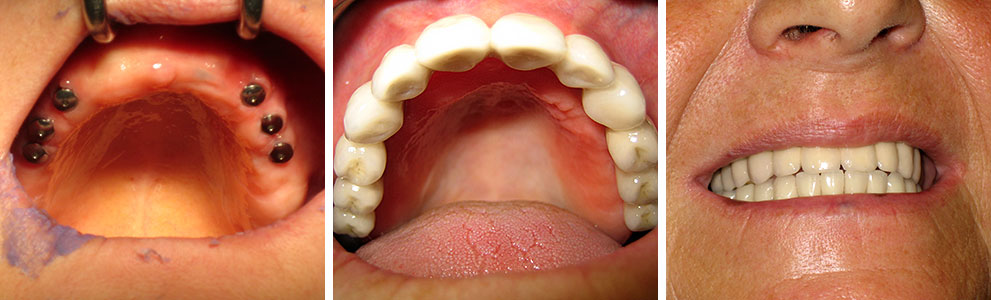

Implantologija